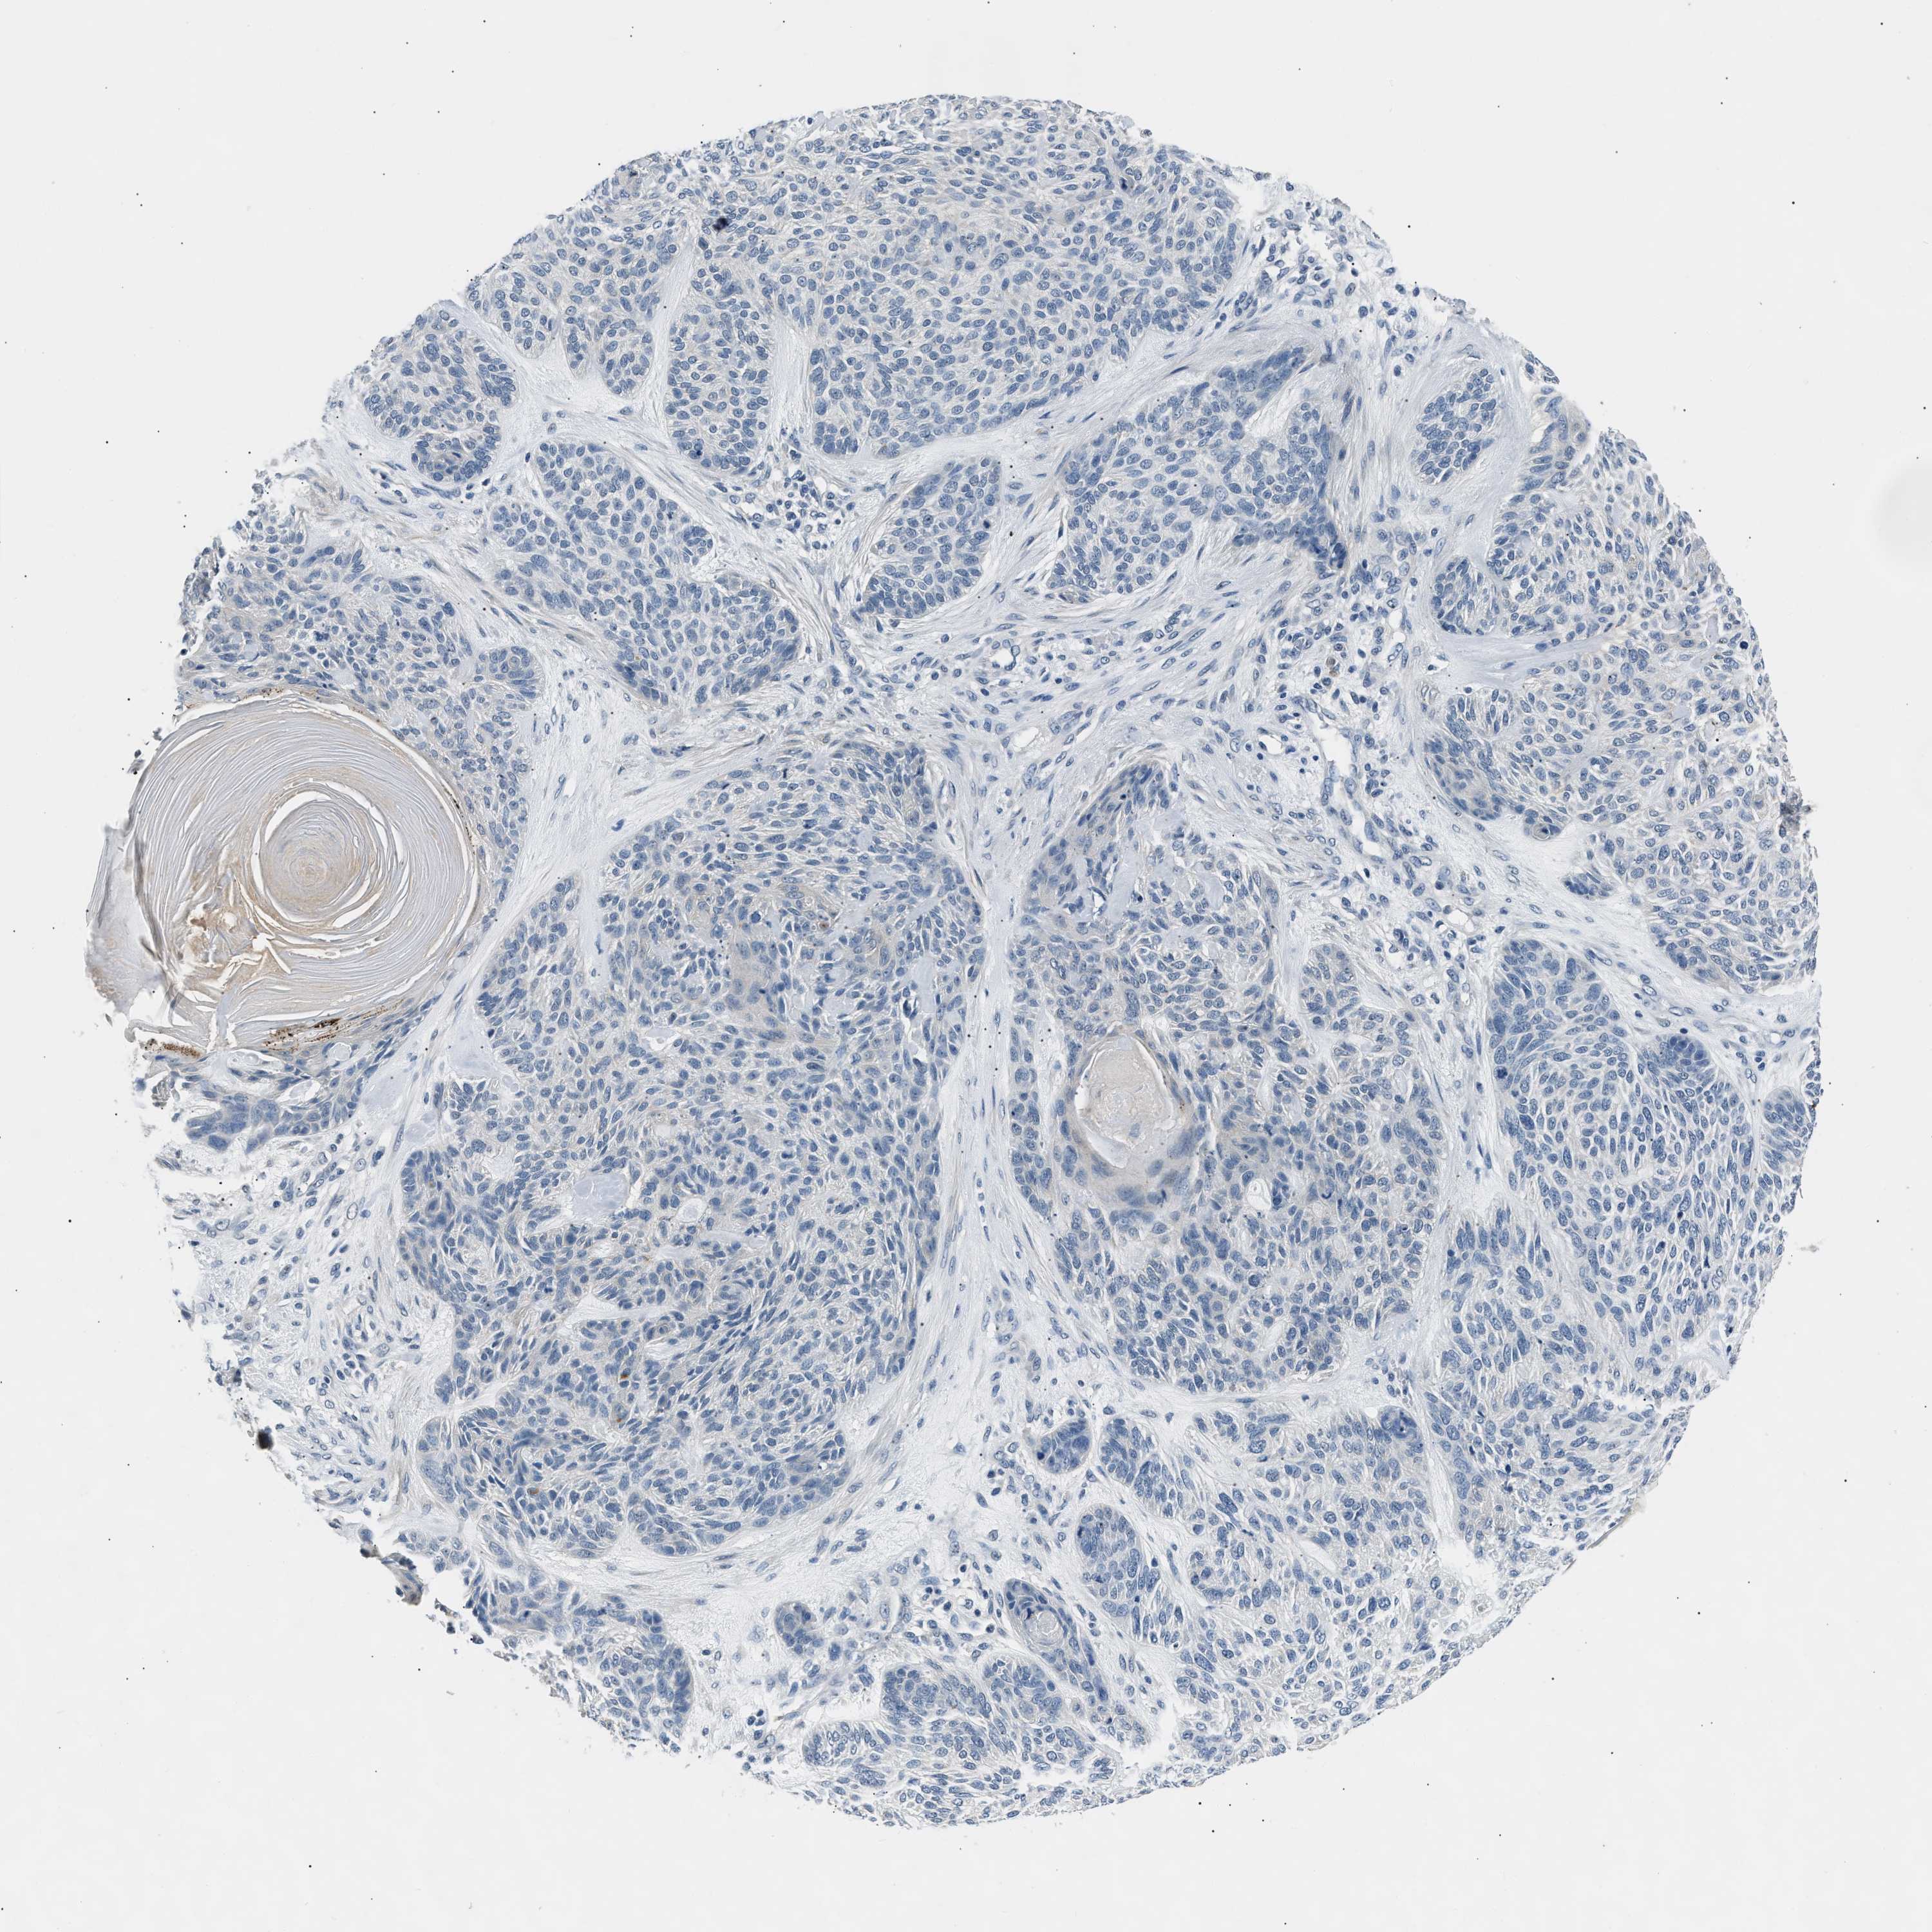

SKIN CANCER - Protein expressioni

A mouse-over function shows sample information and annotation data. Click on an image to view it in a full screen mode. Samples can be filtered based on level of antibody staining by selecting one or several of the following categories: high, medium, low and not detected. The assay and annotation is described here.

Antibody staining in the annotated cell types in the current human tissue is reported as not detected, low, medium, or high, based on conventional immunohistochemistry profiling in selected tissues. This score is based on the combination of the staining intensity and fraction of stained cells.

Each image is clickable and will lead to virtual microscopy that enables deeper exploration of all samples and also displays staining intensity scores, fraction scores and subcellular localization as well as patient and tissue information for each sample.

Squamous cell carcinoma in situ, NOS

Squamous cell carcinoma, NOS

Squamous cell carcinoma, metastatic, NOS

Basal cell carcinoma